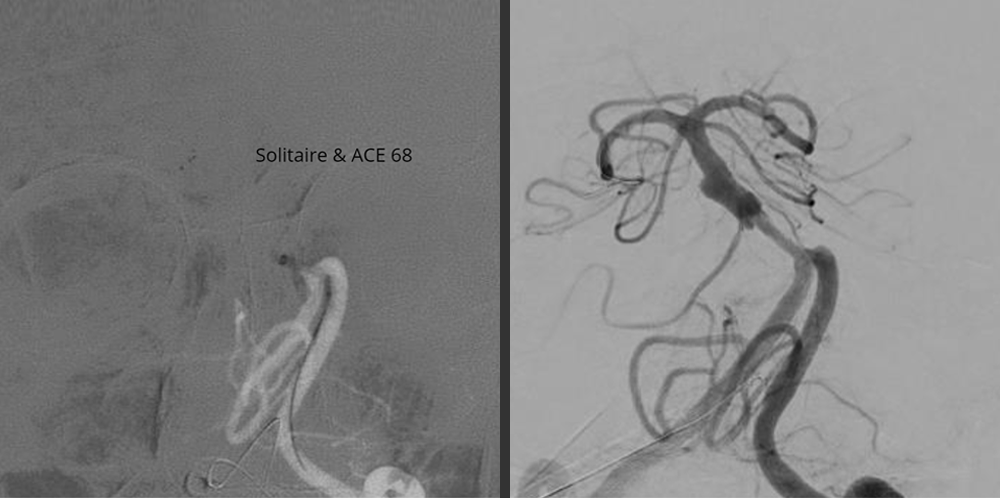

67y/M came with Basilar Artery Thrombosis ( A disease with more then 85% chances of

mortality). Removed clot from brain, placed a stent in his brain artery.

Result – Patient went home

walking just in a span of 7 days.